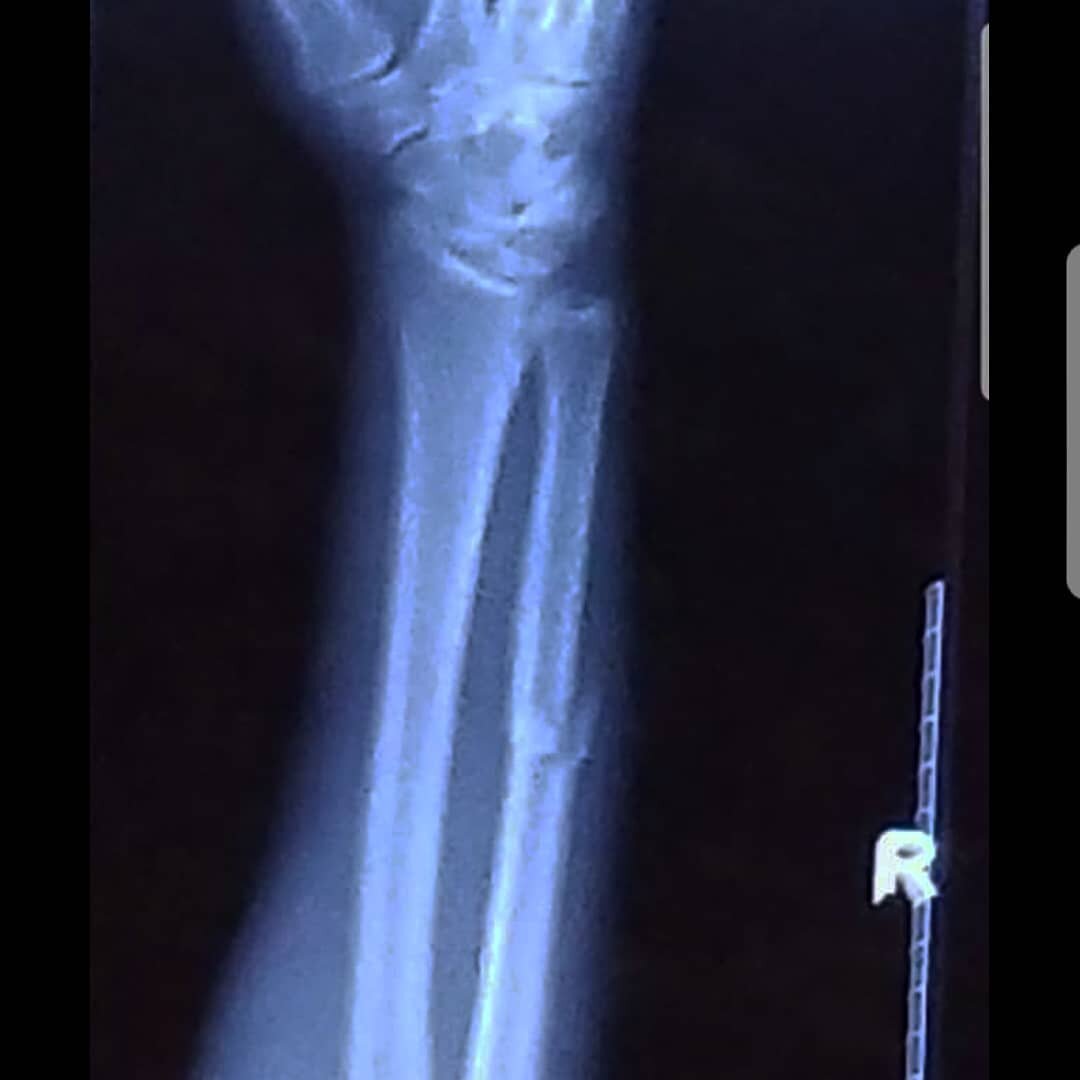

Боец UFS Даниэль Спитц сломал руку в первом раунде поединка с Уолтом Харрисом на турнире UFC Fight Night 131. Об этом спортсмен сообщил в своём «инстаграме», опубликовав фото рентгеновского снимка.

«Нужно отдать должное моему оппоненту Уолту Харрису. Он был лучшим сегодня. Я сломал руку в первые 30 секунд боя, я разочарован результатом, но благодарен за эту возможность. Спасибо всем, кто помогал мне при подготовке к бою», — написал в своём «инстаграме» Спитц.